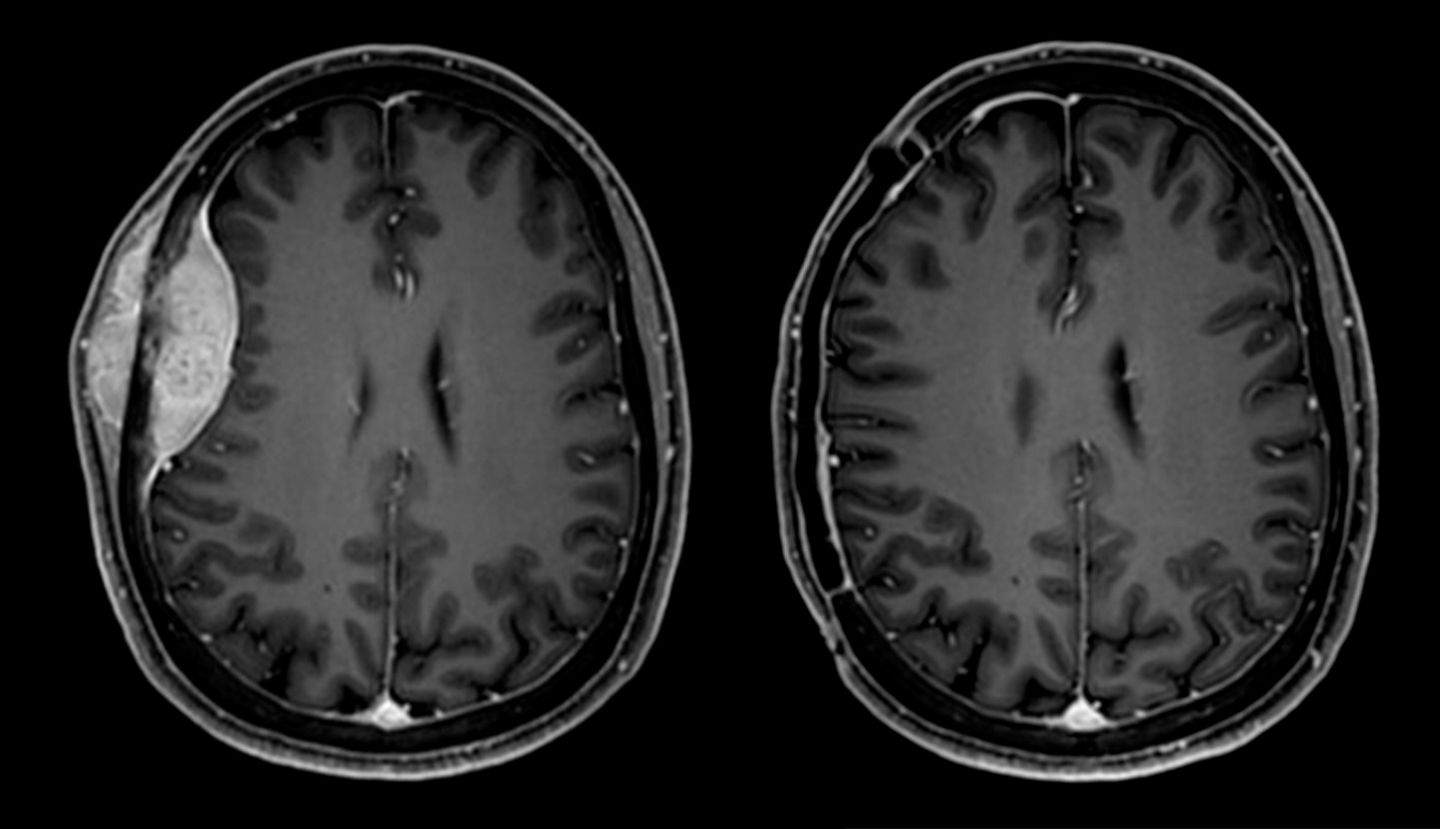

Meningeom vor Operation (links) und nach Entfernung (rechts).